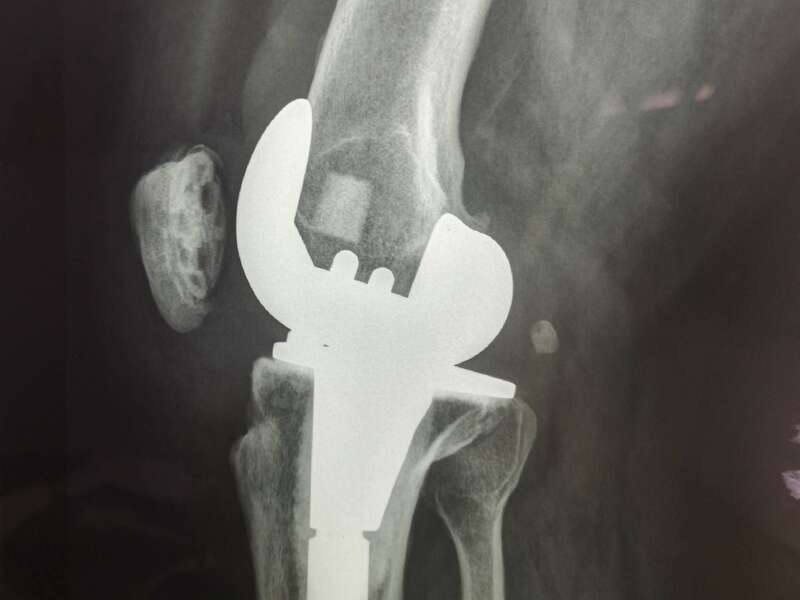

Cas 1. Luxation fémoro-acétabulaire de PTH

Cas 2. Luxation intra-prothétique de PTH